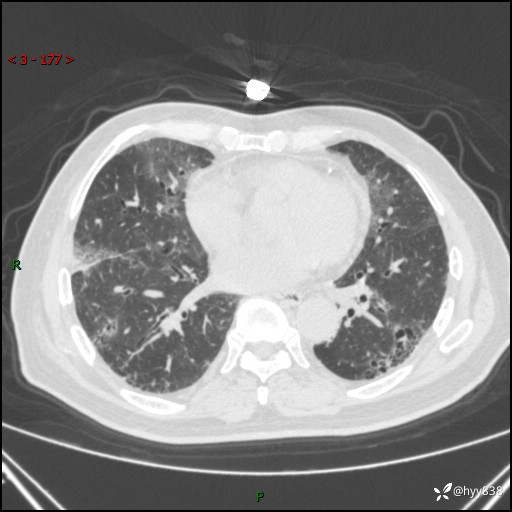

患者性别:男

患者年龄:64岁

简要病史:肝内胆管癌综合治疗后2周余,咳嗽、发热,咳白色泡沫痰。

临床诊断:感染?

讨论:病变性质?